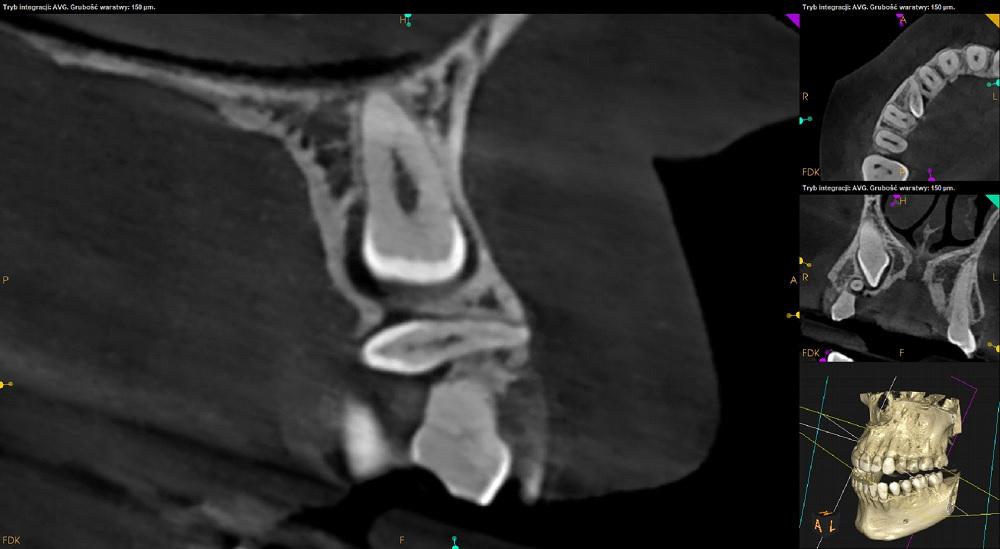

Tomografia szczęka i żuchwa.

Ząb 13 – zatrzymany. Położony pionowo skośnie, koroną skierowany w stronę mezjalną i podniebienną. Zrotowany w stronę dystalną.

Korona zęba 13 przylega do korzenia zeba 12 – resorpcja korzenia niewidoczna. Wierzchołek korzenia zęba 13 zagięty.